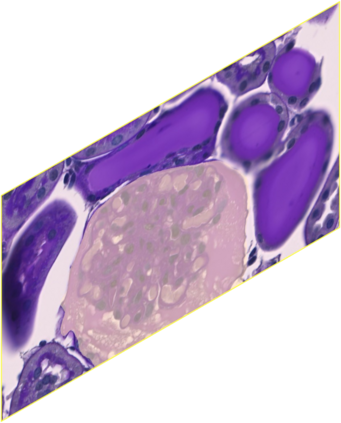

In digital pathology, the traditional method for deep learning-based image segmentation typically involves a two-stage process: initially segmenting high-resolution whole slide images (WSI) into smaller patches (e.g., 256x256, 512x512, 1024x1024) and subsequently reconstructing them to their original scale. This method often struggles to capture the complex details and vast scope of WSIs. In this paper, we propose the holistic histopathology (HoloHisto) segmentation method to achieve end-to-end segmentation on gigapixel WSIs, whose maximum resolution is above 80,000$\times$70,000 pixels. HoloHisto fundamentally shifts the paradigm of WSI segmentation to an end-to-end learning fashion with 1) a large (4K) resolution base patch for elevated visual information inclusion and efficient processing, and 2) a novel sequential tokenization mechanism to properly model the contextual relationships and efficiently model the rich information from the 4K input. To our best knowledge, HoloHisto presents the first holistic approach for gigapixel resolution WSI segmentation, supporting direct I/O of complete WSI and their corresponding gigapixel masks. Under the HoloHisto platform, we unveil a random 4K sampler that transcends ultra-high resolution, delivering 31 and 10 times more pixels than standard 2D and 3D patches, respectively, for advancing computational capabilities. To facilitate efficient 4K resolution dense prediction, we leverage sequential tokenization, utilizing a pre-trained image tokenizer to group image features into a discrete token grid. To assess the performance, our team curated a new kidney pathology image segmentation (KPIs) dataset with WSI-level glomeruli segmentation from whole mouse kidneys. From the results, HoloHisto-4K delivers remarkable performance gains over previous state-of-the-art models.